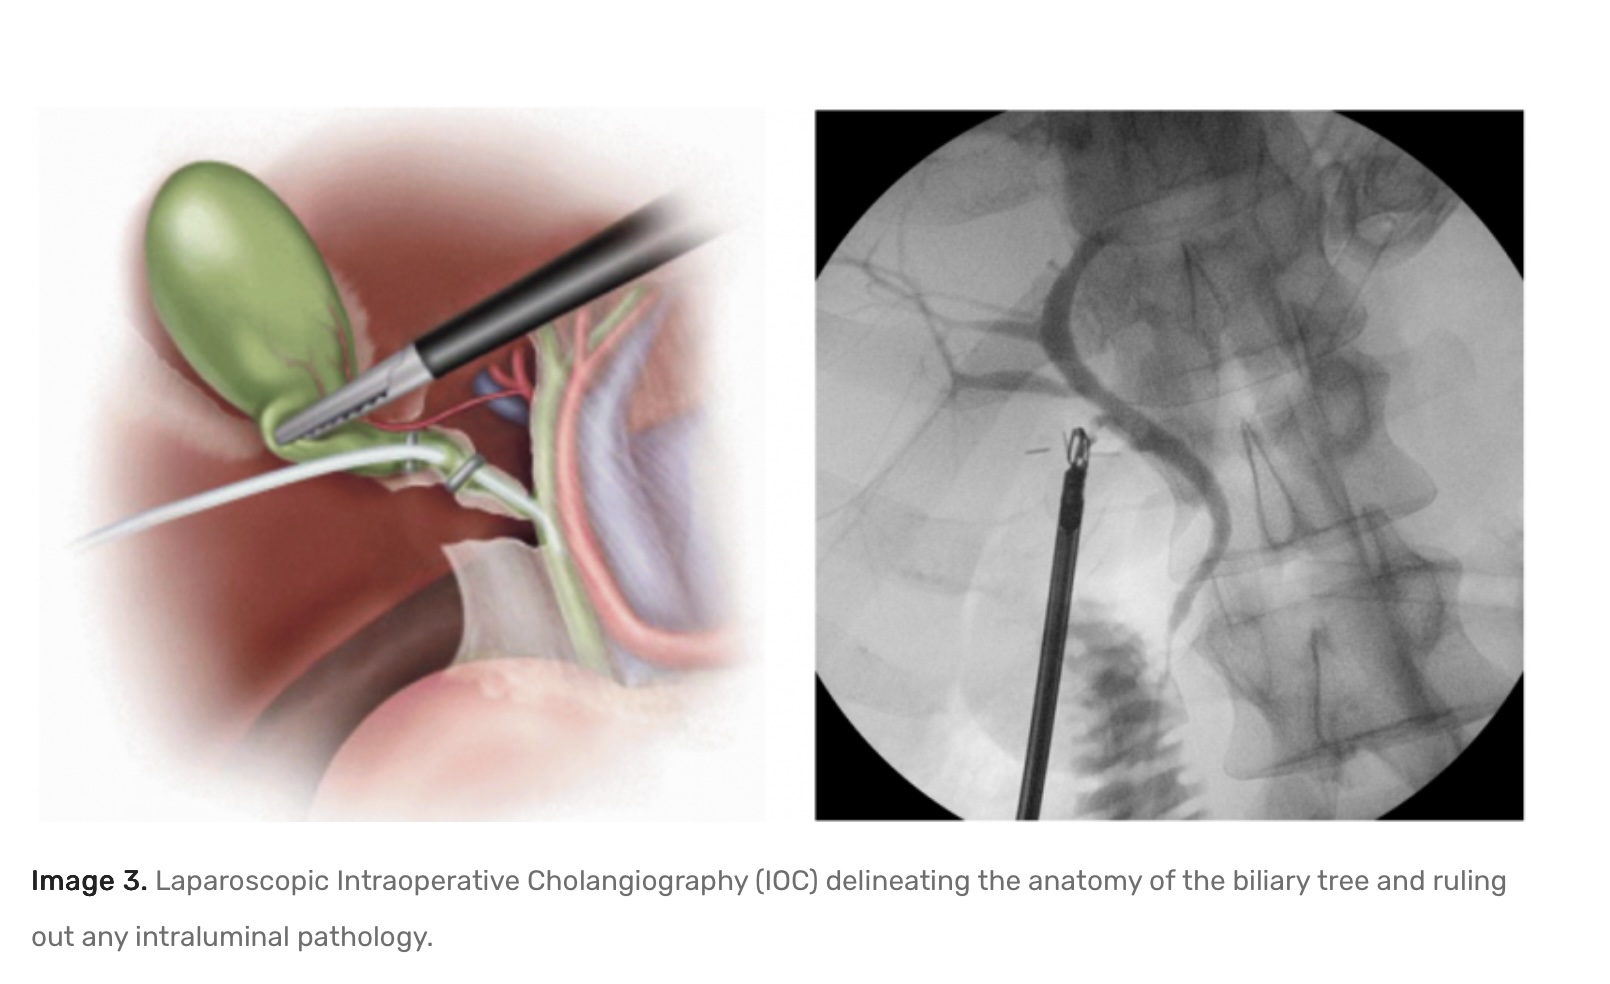

For most patients, laparoscopic cholecystectomy is the recommended treatment. This minimally invasive procedure involves:

• Tiny incisions instead of a large open cut.

• Use of a camera and specialised instruments.